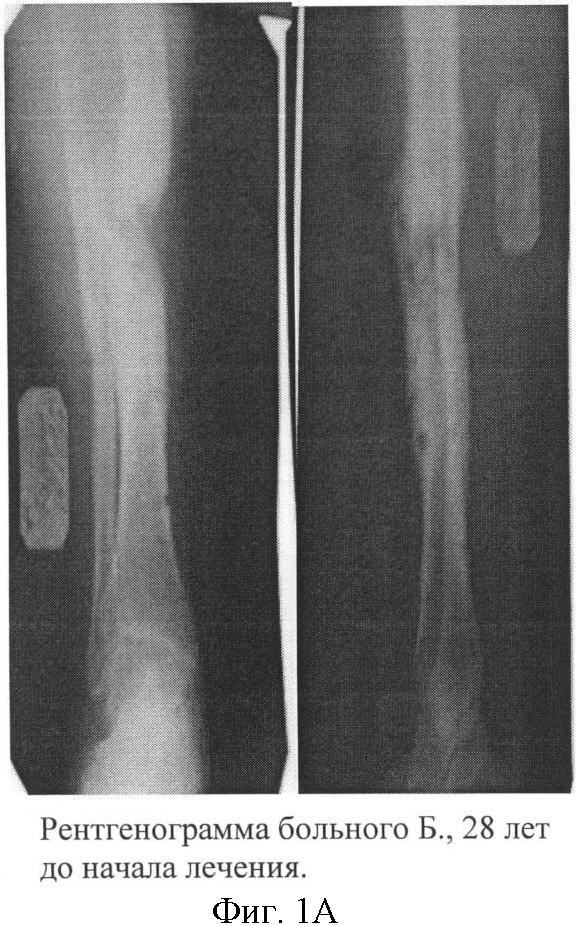

Больной Б., 28 лет, находился на лечении в хирургическом отделении МУЗГКБ 2 с диагнозом: «Хронический посттравматический остеомиелит левой большеберцовой кости в средней трети, свищевая форма; ложный сустав с дефектом костной ткани в средней трети левой большеберцовой кости». Из анамнеза: травма 3 года назад – открытый оскольчатый перелом костей левой голени в средней трети. При поступлении выполнен металлоостеосинтез. Послеоперационный период осложнился развитием остеомиелита. Неоднократно проводились санирующие операции и реостеосинтез, костная аутопластика без эффекта. У больного сохранялся свищ с гнойным отделяемым, больной передвигался с использованием костылей без опоры не конечность. Рентгенологически признаки ложного сустава (фиг.1А). 20.09.07 г. выполнена операция – иссечение свища, некрсеквестрэктомия, дренирование остеомиелитического очага. Иммобилизация гипсовой повязкой. После купирования признаков острого воспалительного процесса выполнены последовательные трансплантации МНК и МСК по описанной схеме. Послеоперационная рана зажила первичным натяжением, признаков воспалительного процесса за период наблюдения не было. Через 3 месяца после имплантации, клинически перелом консолидировался, гипсовая повязка снята. На контрольной рентгенограмме: выраженная костная мозоль по внутренней поверхности средней трети левой большеберцовой кости. Периостальная реакция не отмечается (фиг.1Б). В течение 6 месяцев признаков обострения остеомиелита не было. Больной ходит, не используя дополнительные средства опоры.